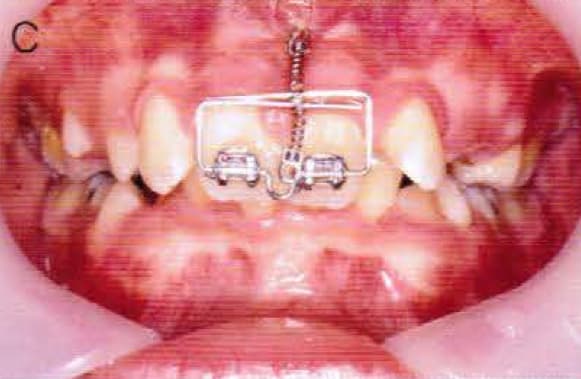

Merci jt2000, seespan et inset pour votre aide. Voici finalement le dispositif que l'on a choisi car je voulais me servir de l'implant comme ancrage.

je vous montrerai l'evolution, favorable ou.... défavorable.

je suis a l'écoute des ortho pour leurs conseils et critiques...

A virskn - Eugenol

B c15bbz - Eugenol

C abqhrm - Eugenol